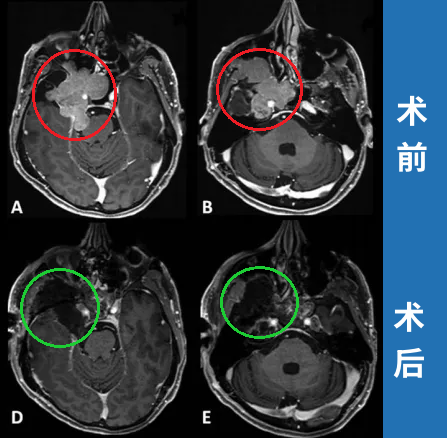

岩斜区位于颞骨岩部背面与枕骨斜坡部的岩斜裂汇合处,从岩骨尖至颈静脉孔。内侧至斜坡中线,外侧至第Ⅴ、Ⅶ和Ⅷ脑神经,上缘为鞍背,下缘为颈静脉孔水平;下方为枕骨大孔区。岩斜区脑...